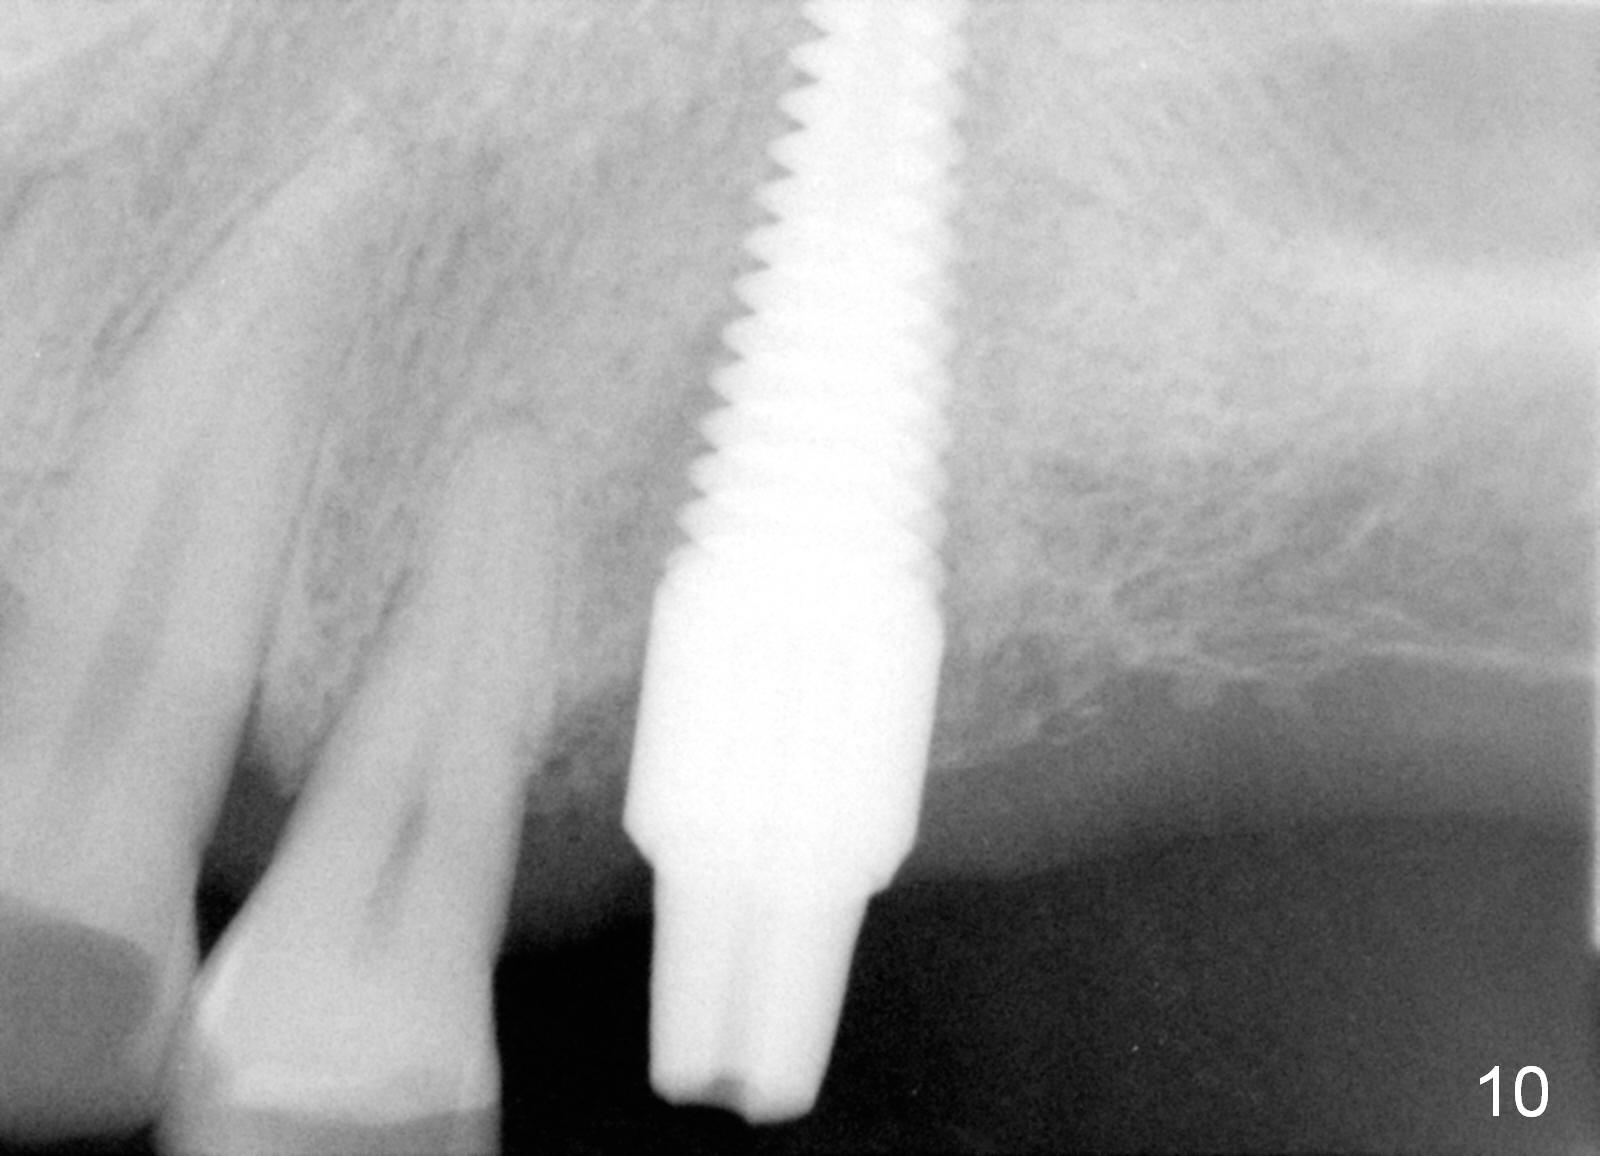

Fig.5 is an illustration showing the socket after extraction. The osteotomy is intentionally placed distally (Fig.6 arrow: pilot drill). In case the patient agrees to have ortho treatment, there will be space to correct the upper midline (7). If not, a molar crown will be fabricated. By the time a 4.5x20 mm tap is inserted (Fig.7 T), the mesial gap is visible (*). When a 6x20 mm implant is placed (Fig.8 I), bone graft is placed buccally (Fig.2, as planned) and mesially (Fig.8 red circles, as compared to Fig.1). The implant has to be as large and long as 6x20 mm to get primary stability (insertion torque 50/60 Ncm). The apex of the implant is close to the sinus floor (Fig.8 ^) or in fact the nasal floor (Fig.9 N). There appears bone growth in the mesial gap 3 months postop (Fig.10 *). There is no bone loss 2.5 years post cementation (Fig.11).